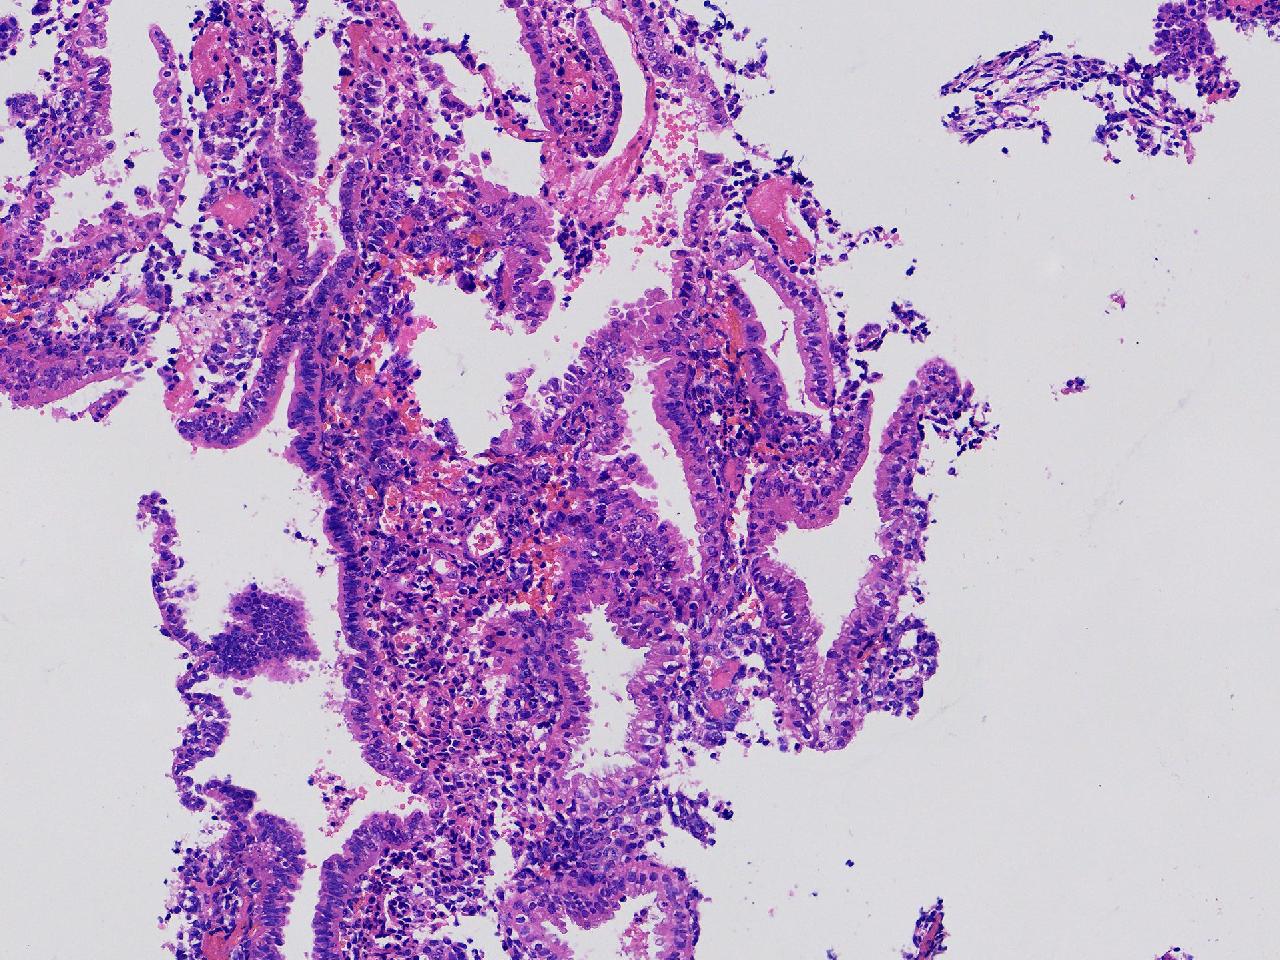

性别

女

年龄

45岁

临床诊断

阴道不规则出血20余天,

一般病史

彩超示:宫腔内见约41X11毫米的不均质回声区。宫腔镜示:宫腔形态正常,内膜粉红,不规则增厚。

标本名称

子宫内膜

大体所见

灰粉色不整形软组织多块,1.5X1X0.6厘米。

图1

分泌反应子宫内膜,伴有出血。

晚泌期及月经早期改变,局部呈啫酸性乳头状化生改变。